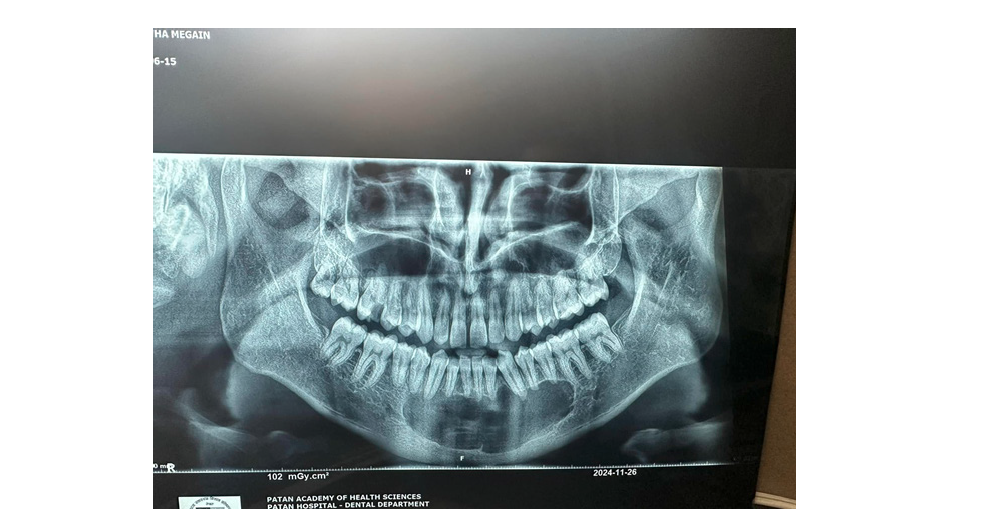

Panoramic radiography provides a two-dimensional depiction of the curved maxillary and mandibular dental arches and serves as a valuable initial tool for evaluating odontogenic lesions, including OKCs. It assists in assessing lesion location, size, morphology, margins and overall extent. However, its diagnostic capability is limited by inherent drawbacks such as magnification, geometric distortion and superimposition of anatomical structures. Consequently, three-dimensional imaging is often requiredparticularly for larger lesions-to obtain more accurate preoperative information. On panoramic images, OKCs typically present as welldefined unilocular or multilocular radiolucent lesions bordered by a corticated rim (Figure 1). The unilocular pattern is more frequently observed, whereas multilocular lesions occur in roughly 30% of cases and are more common in the mandible [9]. In mandibular unilocular OKCs, a few thin or incomplete internal septa may be visible, a feature more commonly associated with larger lesions.

Figure 1:

Mandibular odontogenic kerato-cysts (Okc’s)

a. Cropped panoramic radiograph illustrating a unilocular

lesion in the posterior mandible and ramus, causing mesial

displacement of the impacted third molar (curved arrow).

b. Cropped panoramic radiograph showing a multilocular

lesion involving the posterior mandible and ramus, exhibiting

a characteristic soap-bubble appearance.

A cropped panoramic radiograph reveals a large OKC with well-defined, lobulated borders (arrowheads) occupying the mandibular body. An incomplete internal septum is also visible within the lesion (opposing arrows). Approximately 30% of OKCs are associated with at least one unerupted tooth-most commonly the third molars [9]. This association is observed more frequently in younger patients [15]. The radiographic characteristics of OKCs are not pathognomonic, especially in small unilocular lesions [15]. When a small unilocular OKC appears in the anterior maxillary sextant, it may mimic other odontogenic or non-odontogenic cysts, such as radicular cysts (Figure 1), lateral periodontal cysts or nasopalatine duct cysts [17]. Histologically confirmed OKCs. Cropped panoramic radiographs (a and b) demonstrate two unilocular radiolucent lesions (asterisks) with well-defined, corticated borders (arrowheads) located in the anterior maxilla between the roots of adjacent teeth. The radiographic appearance of these radiolucencies may mimic a radicular cyst. Large mandibular OKCs characteristically grow along the length of the mandible, showing minimal Bucco-lingual expansion, particularly within the mandibular body [15]. On panoramic radiography, this growth pattern typically presents as an extensive radiolucent lesion with significant mesiodistal extension and little or no cortical expansion (Figure 1 & 2). In contrast, large maxillary OKCs often produce marked expansion of the alveolar bone and may involve adjacent anatomical structures. Notably, when a maxillary OKC originates in the molar region, extension into the maxillary sinus is commonly observed (Figure 2) [22].